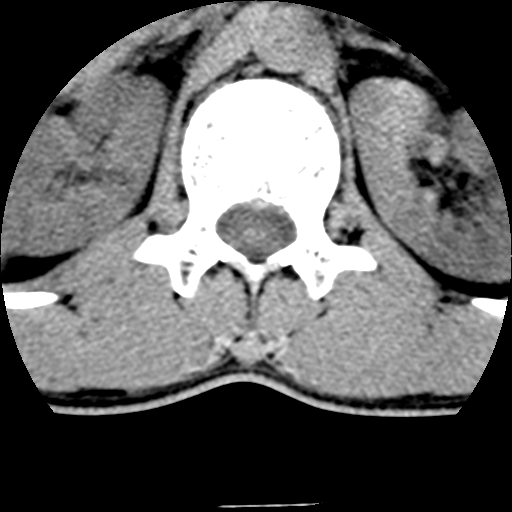

男,31岁,从6米高处坠落伤两天,腰背部疼痛,临床要求ct扫描胸10-腰1。请大家帮忙看看骨质有问题吗?

t12、l1锥体前缘轻度楔形变,平扫示椎体前缘骨小梁欠规整,第9幅图示椎体前缘骨质不连续,结合外伤史考虑椎体轻度压缩骨折。

楼主扫描层厚可能较大,每个椎体只有三个层面.

从所示层面分析,无明确骨折征象,象类似病人我个人会建议mri除外骨挫伤.

从上查骨窗第九片椎体前缘皮质显示断裂.压缩骨折?